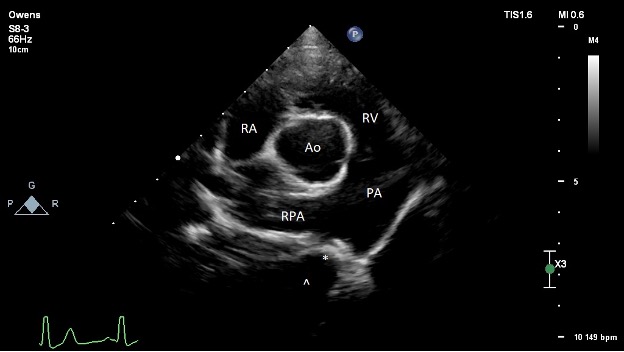

Pre-operative echocardiography (Figure 2):

The left ventricle is moderately dilated at end-diastole and severely dilated at end-systole. Normal fractional shortening and ejection fraction. Normal diastolic assessment. Normal estimated filling pressures.

The left atrium is moderately enlarged.

The right ventricle is normal in size and function.

The right atrium is normal in size.

The aortic valve is structurally normal with no subvalvular ridge of tissue and trace AI. The LVOT velocity is mildly elevated (2.2 m/s). This is thought secondary to the increased stroke volume secondary to the left-to-right shunt given the normal valve appearance.

The mitral valve structure appears normal. There is trace to mild central mitral regurgitation due to annular dilation. Unable to interrogate with spectral Doppler.

The tricuspid valve appears normal. There is trace tricuspid regurgitation.

The pulmonic valve is normal. The RVOT velocity is normal. The PA is dilated due to the continuous high velocity L-R flow.

There is no pericardial effusion.

There is a moderately sized L-to-R shunting patent ductus arteriosus (PDA) present. Minimal ductal diameter measures around 3.5-4.2 mm. There is a dilated ampulla with relatively acute tapering at the pulmonary insertion site, consistent with a Miller type 2 ductal morphology (A vs. B unable to classify on TTE). Normal transductal velocity (5.1 m/s) without evidence of significantly elevated PA pressures. No other congenital defects present.

PICTURE: Figure 2: Pre-operative transthoracic echocardiography image obtained from the right parasternal short axis at the level of the heart base. The ostium of the PDA is denoted with an asterisk (*). The ampulla of the ductus is denoted with a caret (^). RA = right atrium; RV = right ventricle; PA = main pulmonary artery; RPA = right pulmonary artery; Ao = aorta